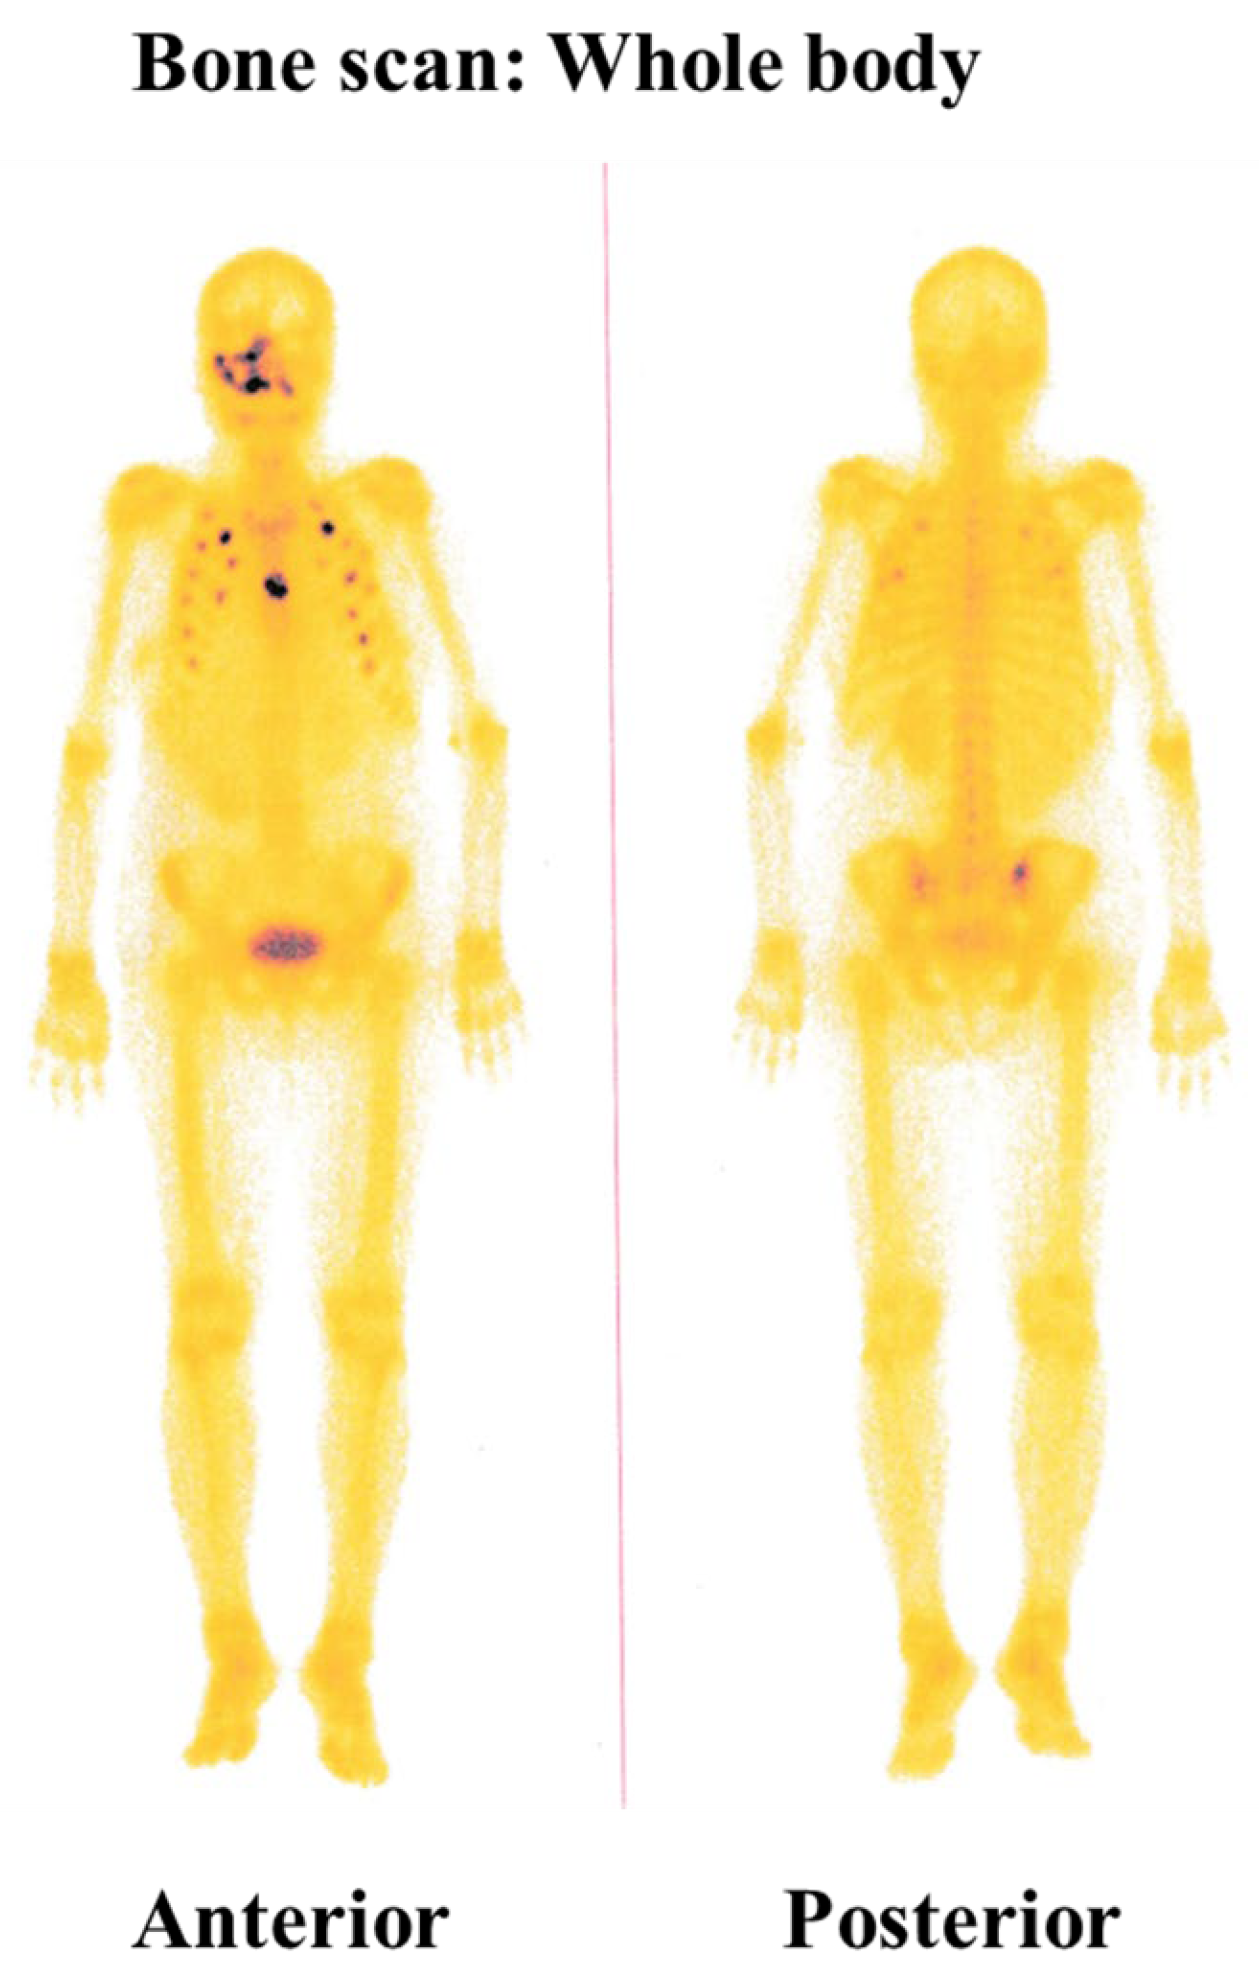

2. Detailed Case Description

| Habiba et al. (present study) | Buccal and palatal mucosa | F | 50 | Yes | Lung, adrenal gland, bone |